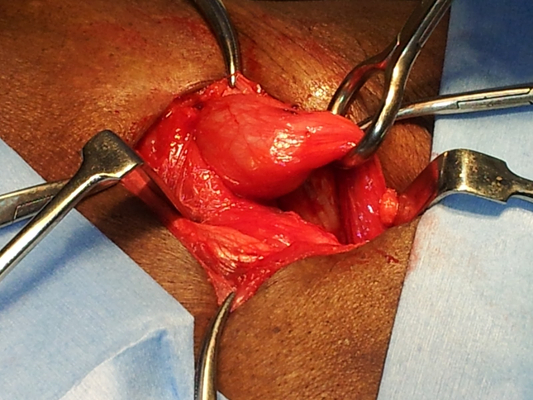

顱內血腫圖片

硬膜下血腫 (7)